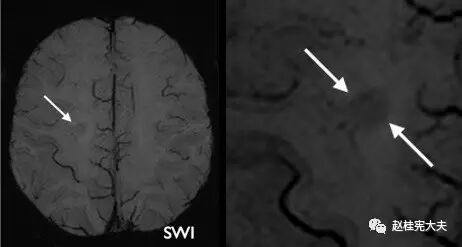

图13. SWI示右侧白质半卵圆中心病灶,箭头示典型“中央静脉征”。

基于常规MRI诊断的局限性,双反转恢复(DIR)序列、相位加权PADRE技术等可提供更多皮质以及软脑膜下炎性病变的信息,DTI可用于识别白质内水的扩散受限,定量白质纤维束破坏和损伤情况等。